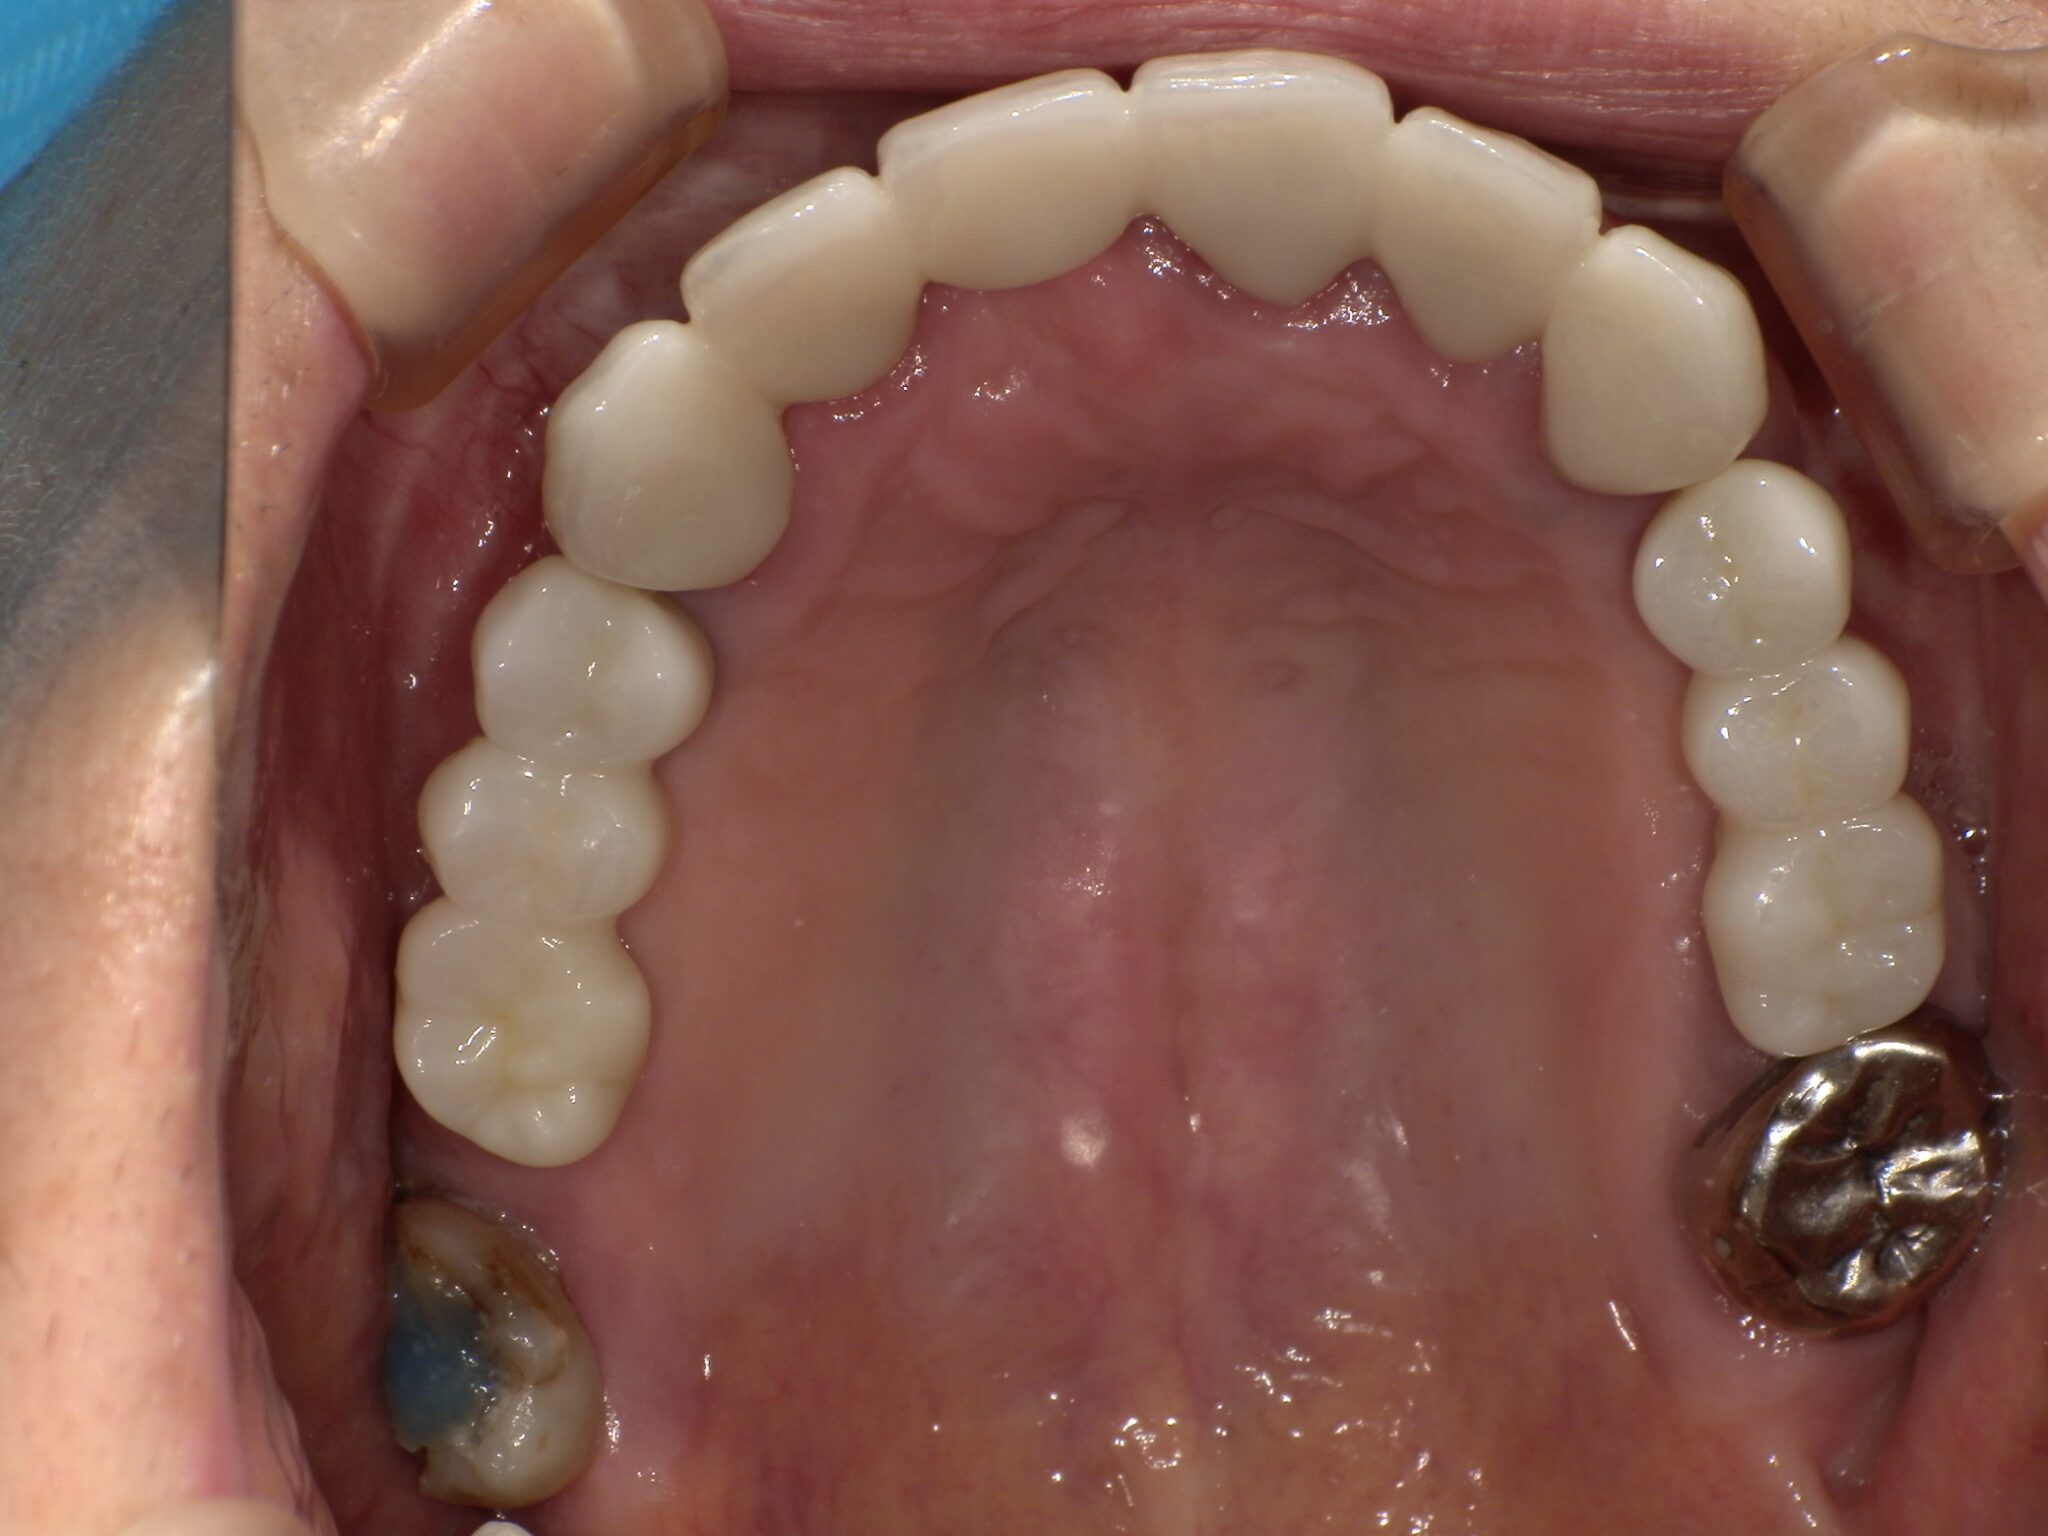

全顎治療症例

| 治療内容 | インプラント埋入(右上4・6,左上4・6,右下6,左下6) ジルコニアBr(右上3―左上3) ジルコニア(右下5,左下5) |

インプラント 1年5ヶ月/13回 ジルコニアBr、ジルコニアクラウン 3ヶ月/10回 |